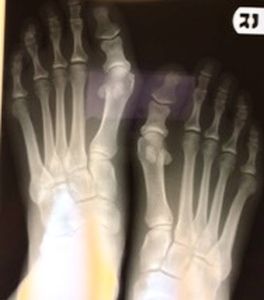

This is a 30 y/o healthy female who has longstanding bilateral 1st/5th MPJ pain and wants a bunion correction of both symptomatic joints involved. She is quite active and her job requires working on her feet 8-10 hours a day. She understands the disability and recovery involved in a bunion correction. After exhausting non-surgical remedies and failure of providing symptom relief of these structural deformities, I will perform surgery on each foot in a separate operative setting.

Pre-op X-rays |

I am concerned about the short proximal phalanx of both great toes. I am considering a double osteotomy (Akin-Austin) on both great toes and a Lapidus fusion of the left 1st met-cunieform joint due to the high IM. I will perform a 5th metatarsal osteotomy of both 5th metatarsals as well to correct the Tailor's bunion. I was considering reducing the length of the 2nd metatarsal for biomechanical reasons to accommodate for the surgical shortening of the 1st ray when the HAV correction procedure is performed on the involved foot. Should I instead try to lengthen the proximal phalanx of the great toe with an opening wedge type osteotomy on the lateral side of the phalanx using a bone graft with fixation?